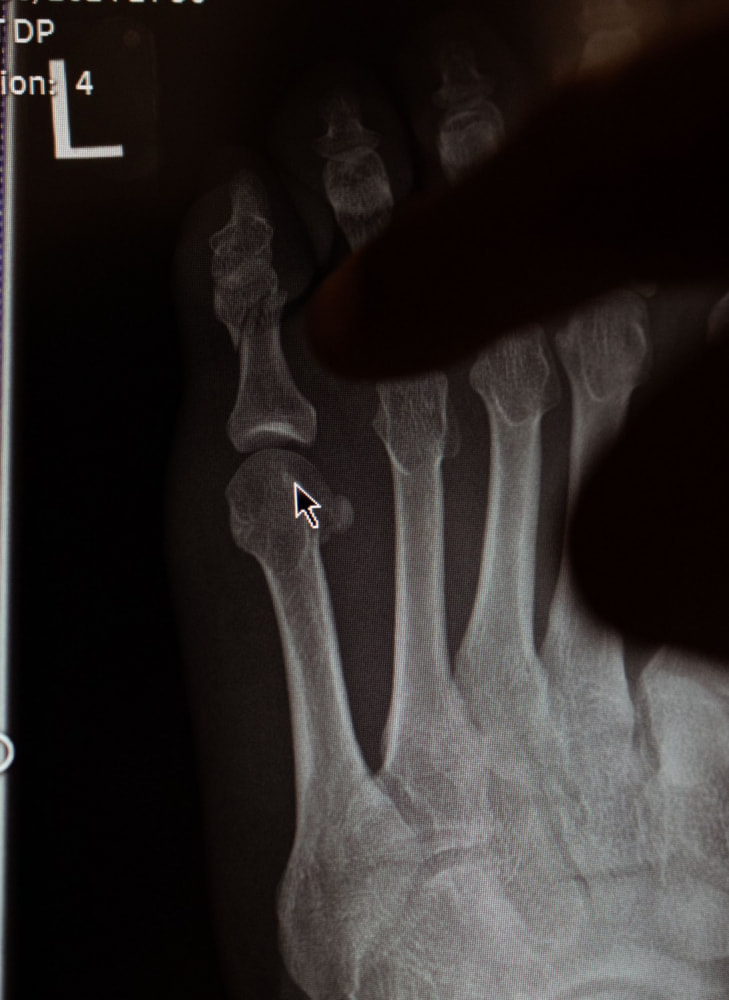

マクレガーが小指骨折で欠場を伝えるレントゲン写真(TheNotoriousMMA)